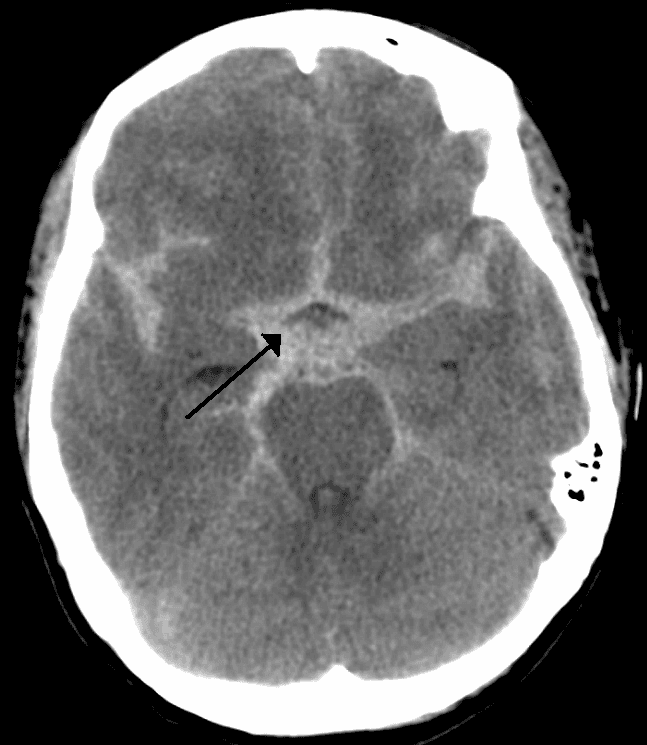

Subarachnoid hemorrhage (SAH) is bleeding into the subarachnoid space—the area between the arachnoid membrane and the pia mater surrounding the brain. Symptoms may include a severe headache of rapid onset, vomiting, decreased level of consciousness, fever, weakness, numbness, and sometimes seizures. Neck stiffness or neck pain are also relatively common. In about a quarter of people a small bleed with resolving symptoms occurs within a month of a larger bleed. SAH may occur as a result of a head injury or spontaneously, usually from a ruptured cerebral aneurysm. Risk factors for spontaneous cases include high blood pressure, smoking, family history, alcoholism, and cocaine use. Generally, the diagnosis can be determined by a CT scan of the head if done within six hours of symptom onset. Occasionally, a lumbar puncture is also required. After confirmation further tests are usually performed to determine the underlying cause. Treatment is by prompt neurosurgery or endovascular coiling. Medications such as labetalol may be required to lower the blood pressure until repair can occur. Efforts to treat fevers are also recommended. Nimodipine, a calcium channel blocker, is frequently used to prevent vasospasm. The routine use of medications to prevent further seizures is of unclear benefit. Nearly half of people with a SAH due to an underlying aneurysm die within 30 days and about a third who survive have ongoing problems. Between ten and fifteen percent die before reaching a hospital. Spontaneous SAH occurs in about one per 10,000 people per year. Females are more commonly affected than males. While it becomes more common with age, about 50% of people present under 55 years old. It is a form of stroke and comprises about 5 percent of all strokes. Surgery for aneurysms was introduced in the 1930s. Since the 1990s many aneurysms are treated by a less invasive procedure called endovascular coiling, which is carried out through a large blood vessel.